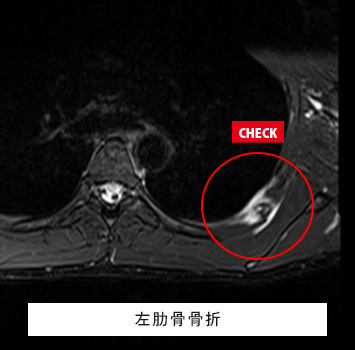

股関節MRIチェック

このような方におすすめします。

• 股関節が痛い

• 股関節が動かしづらい、クリック音がする

• スポーツや仕事で股関節を痛めた、痛みが治らない

筋肉と関節痛みのMRIチェック名古屋なら

レントゲン検査では分からない骨、筋肉、腱、関節唇などの様子が

がたった10分の検査で評価出来ます!

スポーツ選手、左股関節痛が続く、レントゲンで異常なし

転倒後の股関節痛、レントゲンで異常なし

料金:¥17,600(税込)

ご予約はこちら

股関節唇損傷、大腿骨頭壊死症、変形性股関節症、FAI(大腿骨寛骨臼インピンジメント)、関節リウマチなどの炎症性疾患、関節水腫、骨腫瘍、疲労骨折、滑液包炎、感染性股関節炎 など